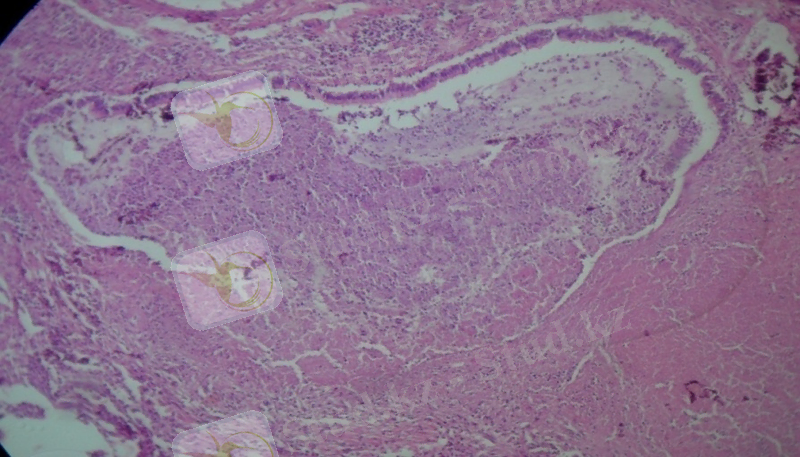

Микроскопиялық зерттеулерде каверналар әдеттегідей үш қабаттан тұрды. Фиброзды қабат жіңішке болды, грануляциялық қабаты нашар жетілген, аз мөлшерде лимфоидты элементтерден, нейтрофильдерден, макрофагтардан тұрады, бірлі-жарым эпителиоидты және Пирогов-Лангханс жасушалары кездесті. Казеозды некроз қабаты өте көлемді болды. Кавернаның айналасындағы өкпе паренхимасында көптеген себінді ошақтар анықталды, олардың ортаңғы бөліктерінде казеозды некроз, айналасында сирек орналасқан эпителиоидты және Пирогов-Лангханс типті көп ядролы алып жасушалар анықталады. Перикавитарлы аймақтарда сегментарлы және полисегментарлы серозды пневмония ошақтары анықталып, серозды экссудаттың казеозды некрозға ұшырауы нәтижесінде сегментарлы казеозды пневмония дамыған (1 сурет) . Казеозды ошақтардың ортаңғы бөлімдерінде ыдырау үрдістері дамып, жаңадан пневмониогенді қуыстар пайда болды. Казеозды массаларда көп мөлшерде ТМ анықталды (2 сурет) . Үлкен бронхтарда гранулематозды мезобронхиттер дамыды, ал субсегментарлы және кіші бронхтарда казеозды бронхиттер анықталды, олардың қабырғаларының сегментарлы және тоталды еруі байқалды (3 сурет) .

1-ші сурет. Казеозды пневмония ошағы. 2-ші сурет. Өкпе тінідегі ТМ жинақталуы

Гематоксилин және эозин бояуы. Ziehl-Neelsen бояуы.

Үлкейту х 200. Үлкейту х 400.